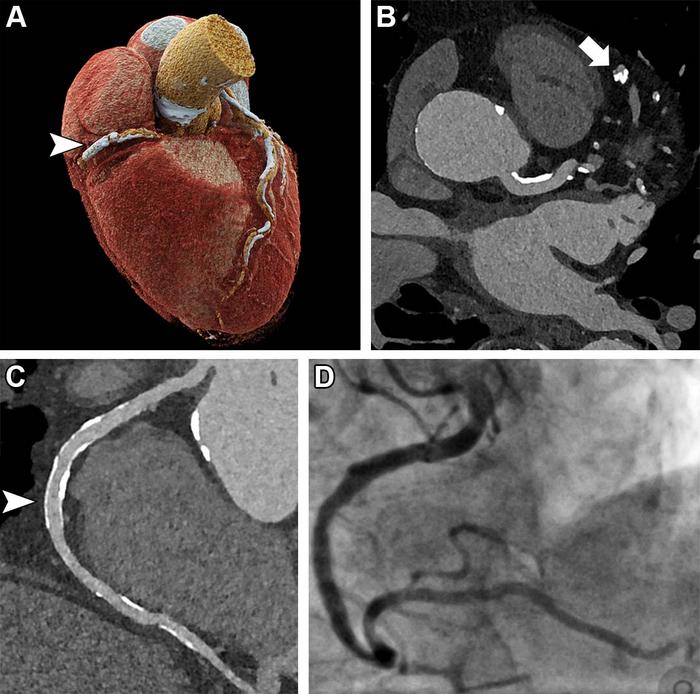

OAK BROOK, Ill. – New ultra-high-resolution CT technology enables excellent image quality and accurate diagnosis of coronary artery disease in high-risk patients, a potentially significant benefit for people previously ineligible for noninvasive screening, according to a study published in Radiology , a journal of the Radiological Society of North America ( RSNA ).

Coronary artery disease is the most common form of heart disease. Coronary CT angiography (CCTA) is highly effective for ruling out coronary artery disease in patients at low or intermediate risk for the disease. Unfortunately, CCTA in a high-risk population is difficult due to a high prevalence of coronary calcifications and stents. Coronary calcifications tend to “bloom” on CCTA, making them appear more extensive than they really are. This results in overestimation of blockages and plaque and false-positive results.

Ultra-high-resolution coronary CT angiography (UHR-CCTA) is a promising tool for the noninvasive assessment of patients at high risk for coronary artery disease. Because it uses recently introduced photon-counting CT scanners, it has not been extensively studied.

Dr. Hagar and colleagues compared the diagnostic accuracy of UHR-CCTA with that of the reference standard of invasive coronary angiography (ICA) in 68 patients. The patients had severe aortic valve stenosis, a common, serious valve disease that reduces or blocks blood flow from the heart to the aorta.

UHR-CCTA was highly sensitive and specific for coronary artery disease detection. It delivered a median overall image quality score of 1.5 on the 5-point Likert scale, where 1 is excellent and 5 is nondiagnostic. Almost 80% of segments rated as good or excellent.